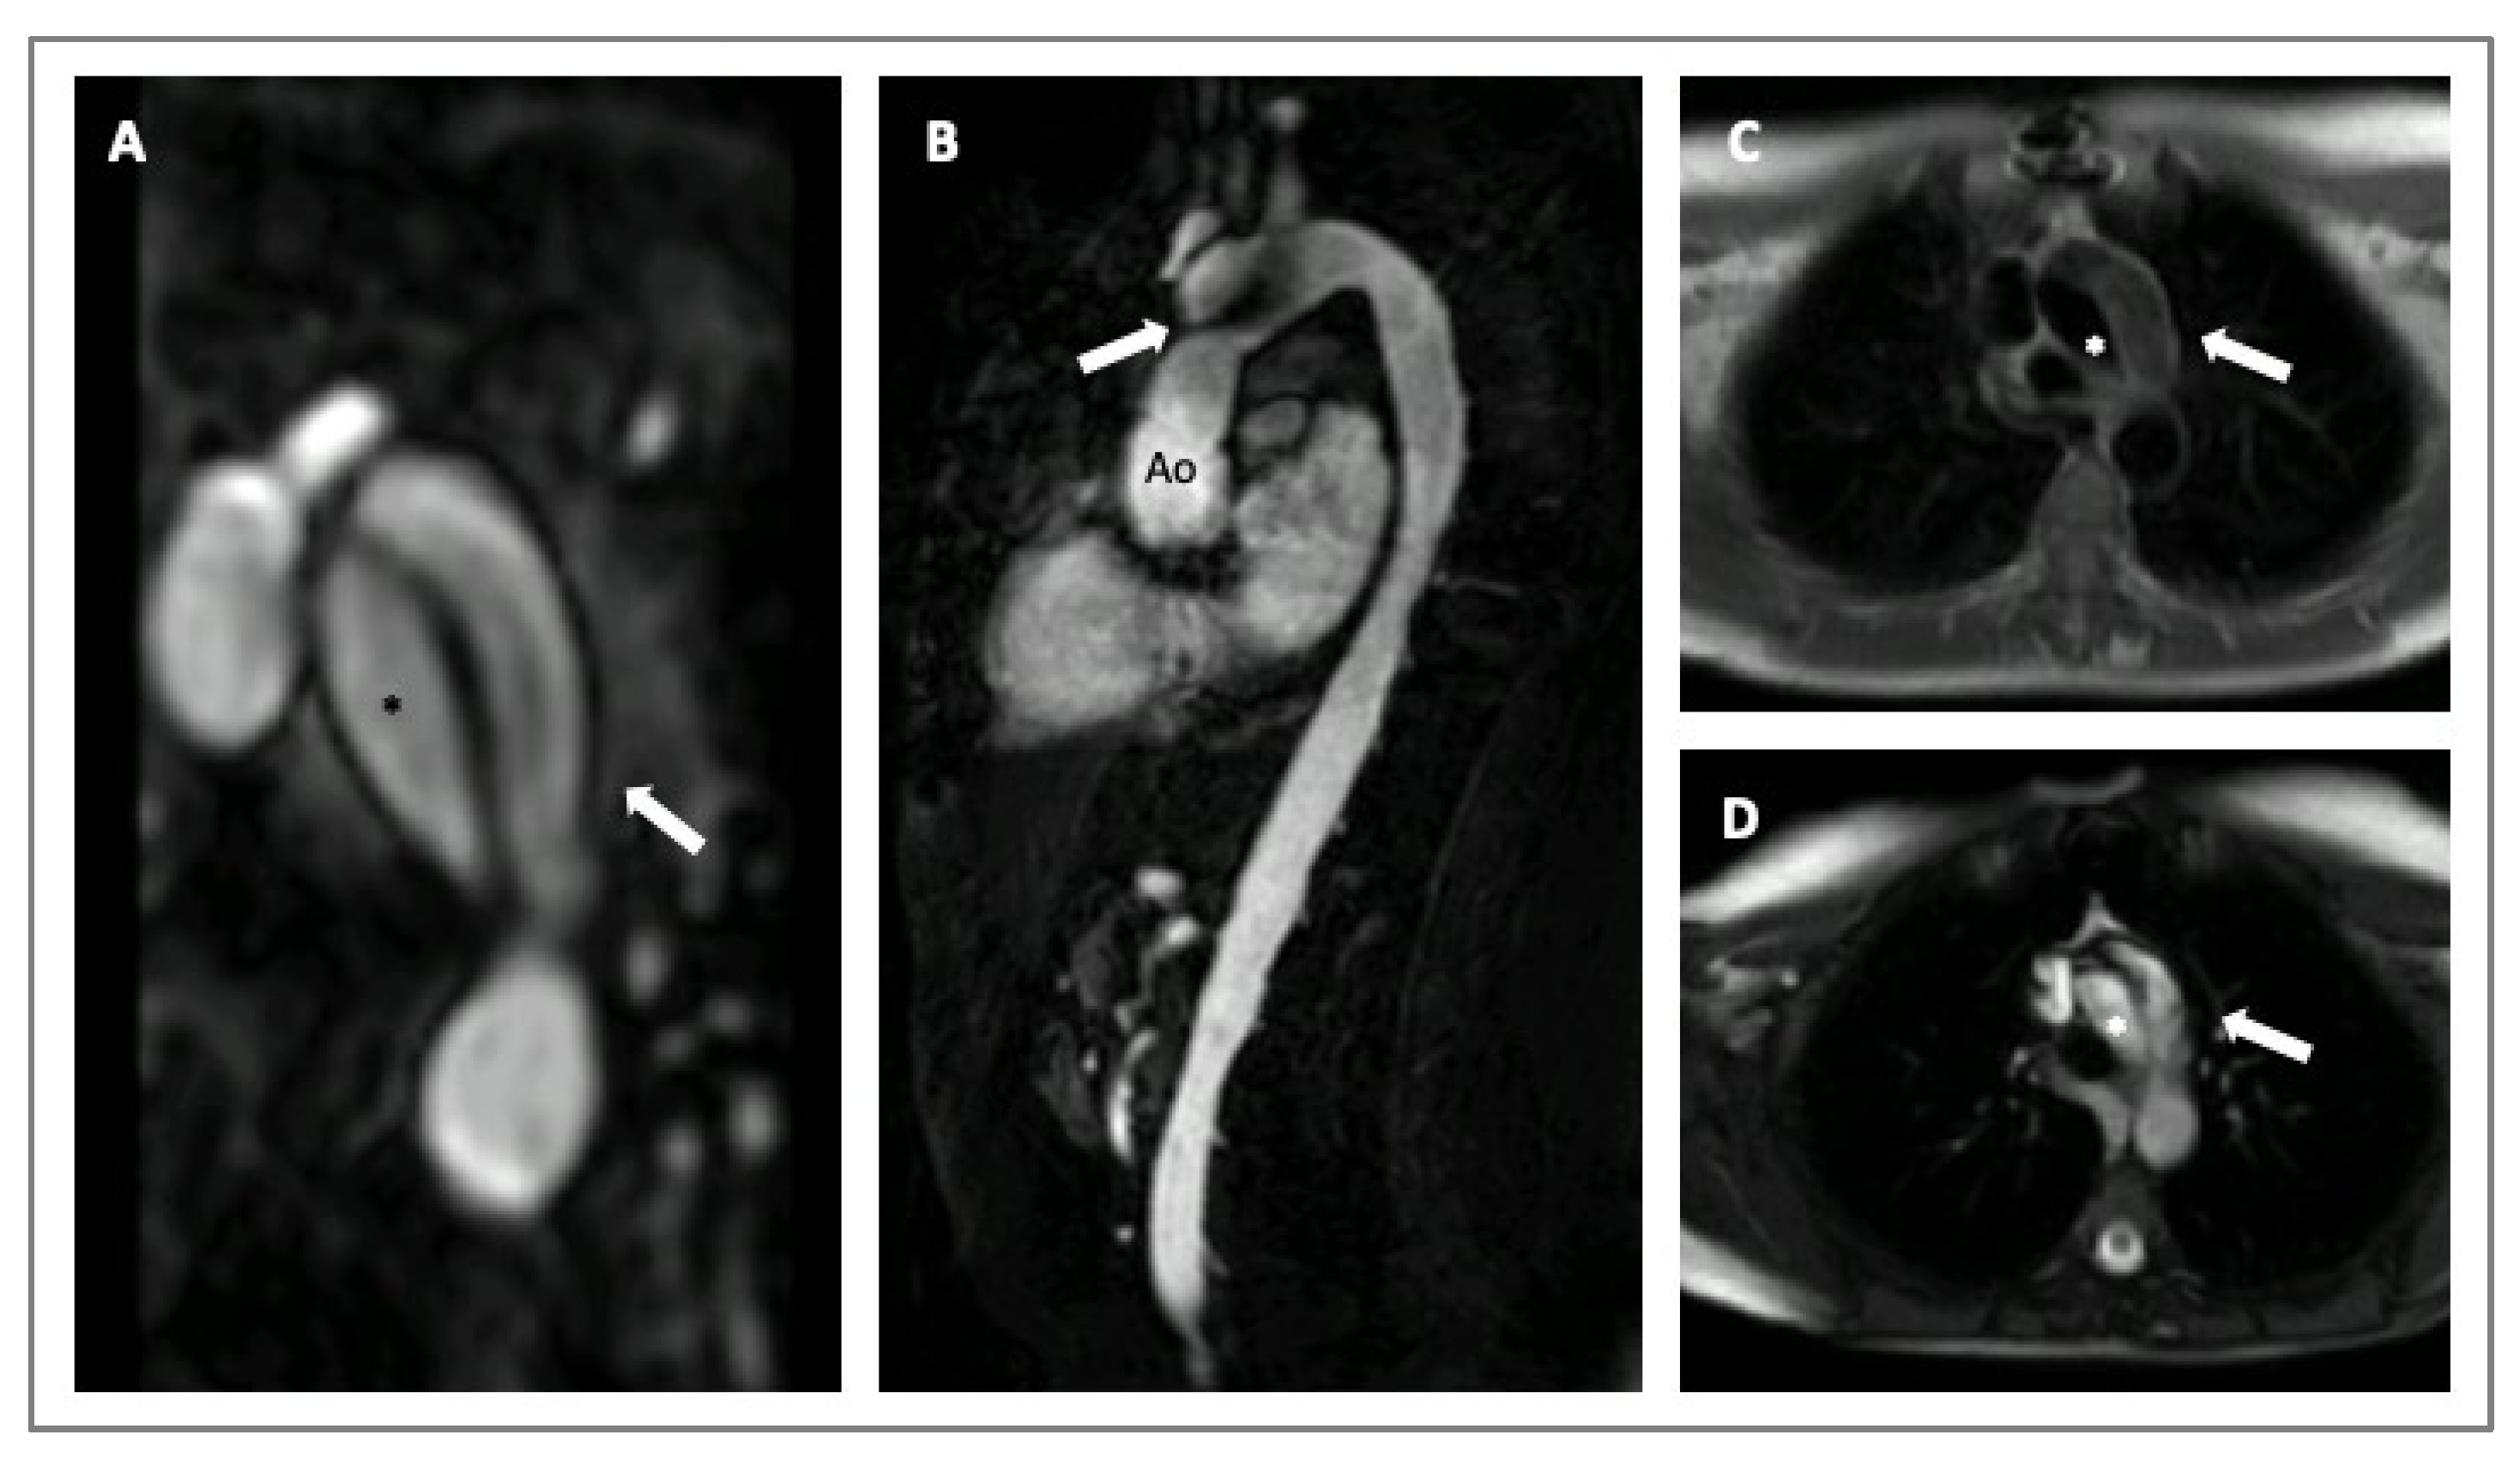

4. Imaging in HTADs

- Lenz, A.; Warncke, M.; Wright, F.; Weinrich, J.M.; Schoennagel, B.P.; Henes, F.O.; Adam, G.; von Kodolitsch, Y.; Schoen, G.; Bannas, P. Longitudinal follow-up by MR angiography reveals progressive dilatation of the distal aorta after aortic root replacement in Marfan syndrome. Eur. Radiol. 2023, 33, 6984–6992. [Google Scholar] [CrossRef]

- Steinbrecher, K.L.; Marquis, K.M.; Braverman, A.C.; Ohman, J.W.; Bhalla, S.; Lin, C.Y.; Naeem, M.; Raptis, C.A. Imaging of Genetic Thoracic Aortopathy. Radiographics 2022, 42, 1283–1302. [Google Scholar] [CrossRef]